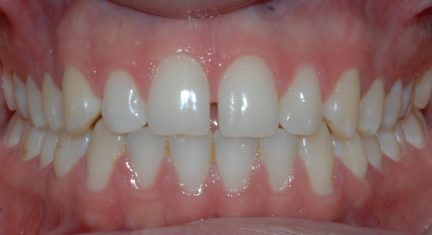

Résultats obtenus

- Relation de classe I maintenue

- Lignes médianes coïncidentes

- Courbe de Spee nivelée

- En raison d'un écart de Bolton, la réduction interproximale était nécessaire dans l'arcade inférieure pour obtenir une relation correcte entre le surplomb et le surplomb. La réduction interproximale établie entre l'incisive centrale supérieure n'a pas été appliqué, de sorte que la fermeture du diastème pouvait avoir un raccord avec les derniers aligners.

État final